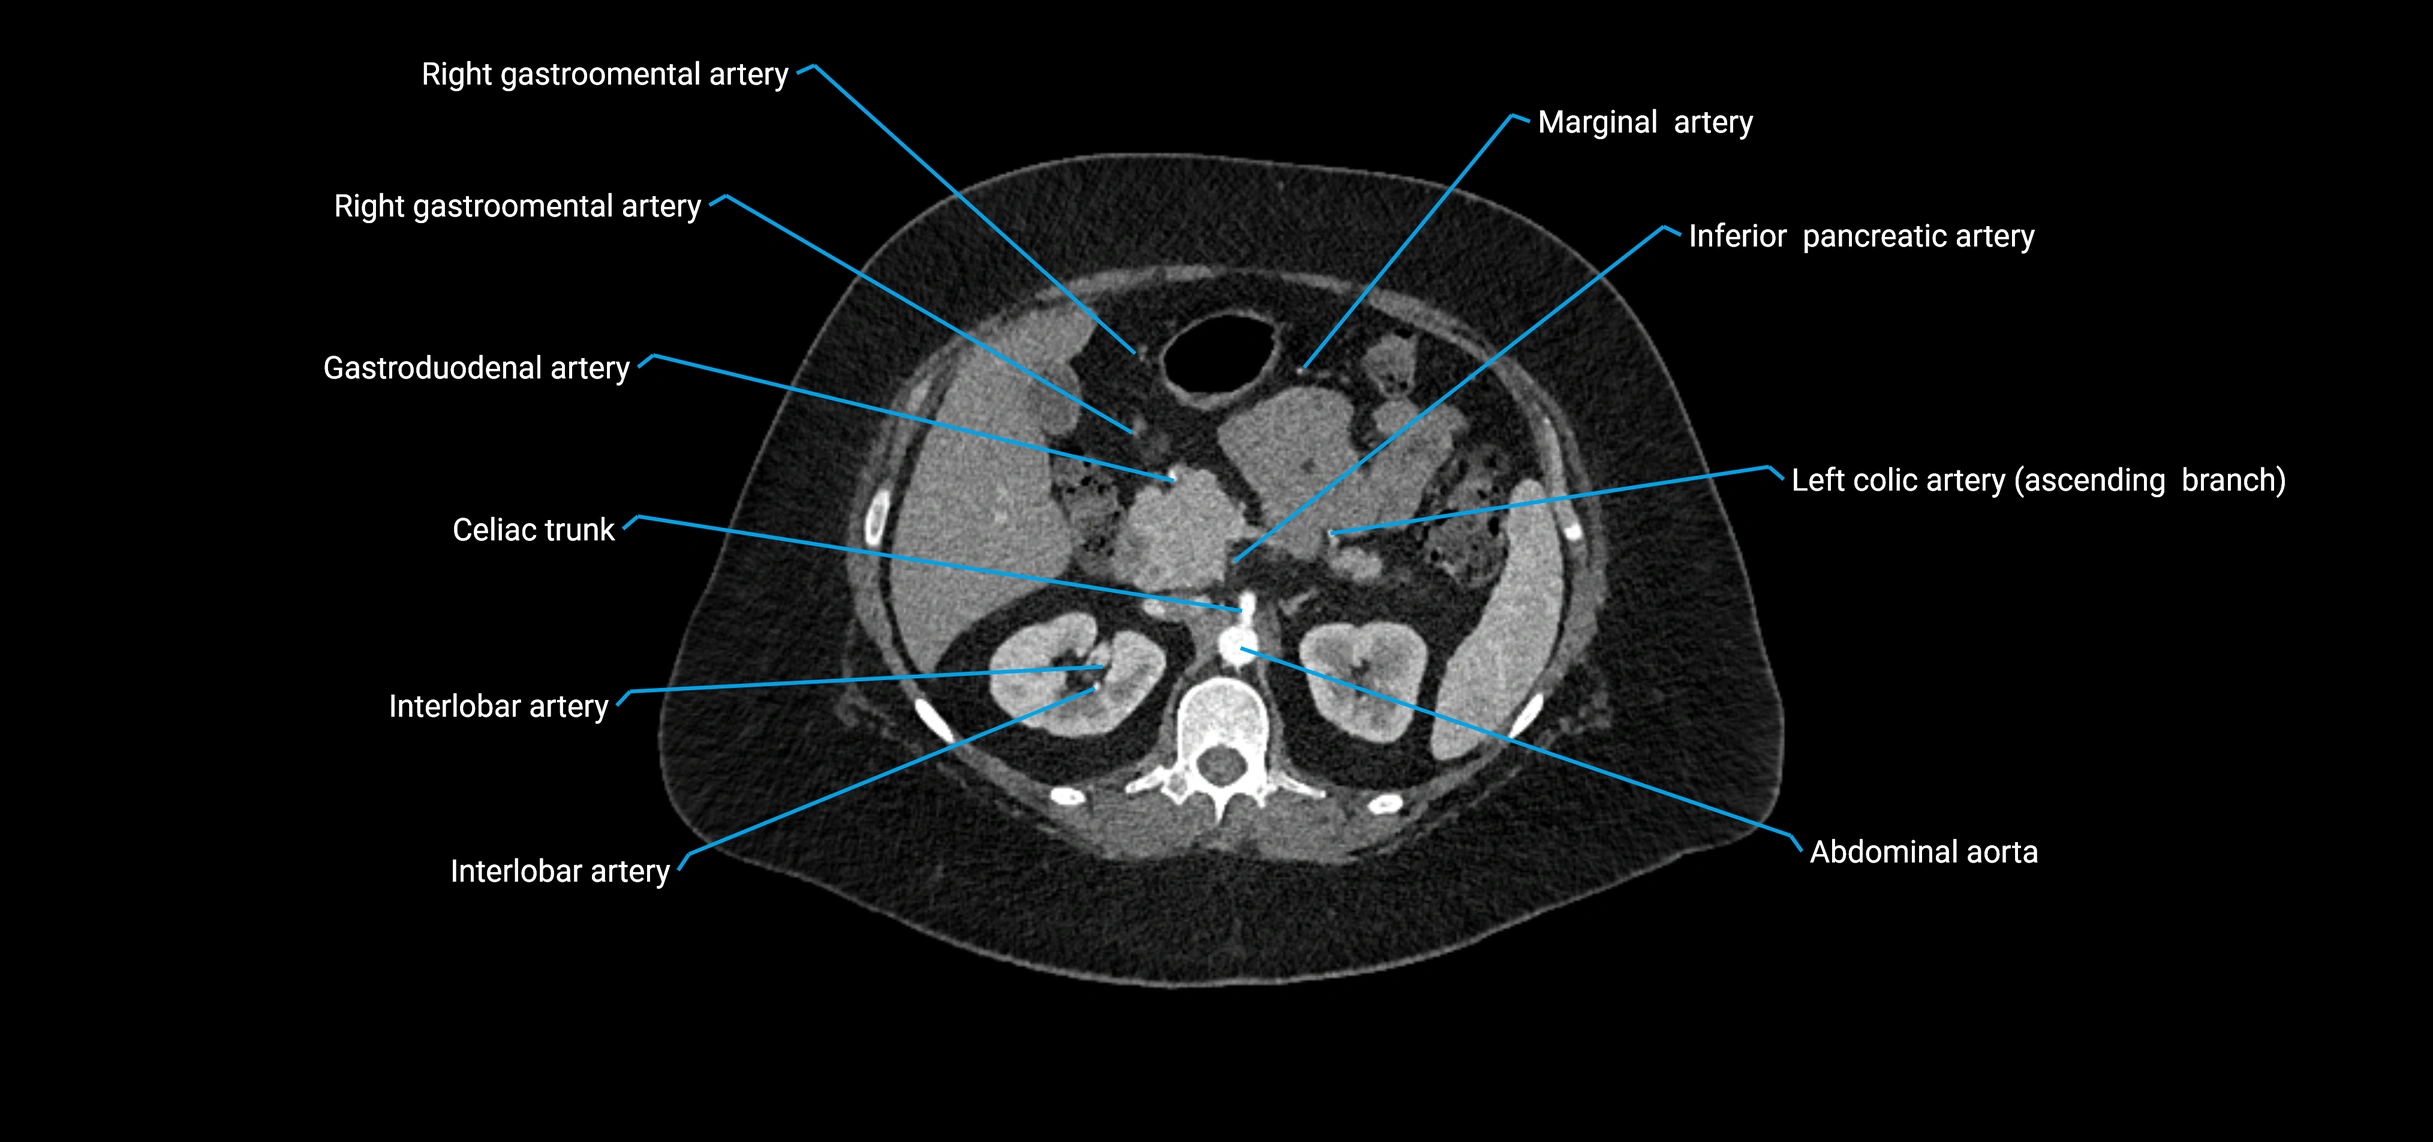

CT images

image

Contrast-enhanced CT (CTA):

• Gold standard for abdominal aortic imaging

• Provides excellent detail of lumen, wall, aneurysm, thrombus, and branch vessels

• Multiplanar and 3D reconstructions help in aneurysm measurement, stent graft planning, and dissection evaluation

• Unpaired visceral branches: celiac trunk, superior mesenteric artery (SMA), inferior mesenteric artery (IMA)